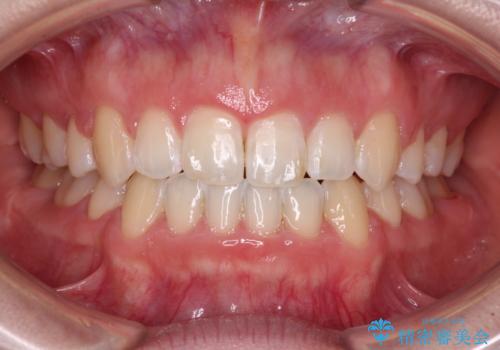

骨格的に下顎骨が前方位にあるため、口元の突出感改善には限界があると思われましたが、唇の閉じにくさが改善するほど引っ込めることができました。